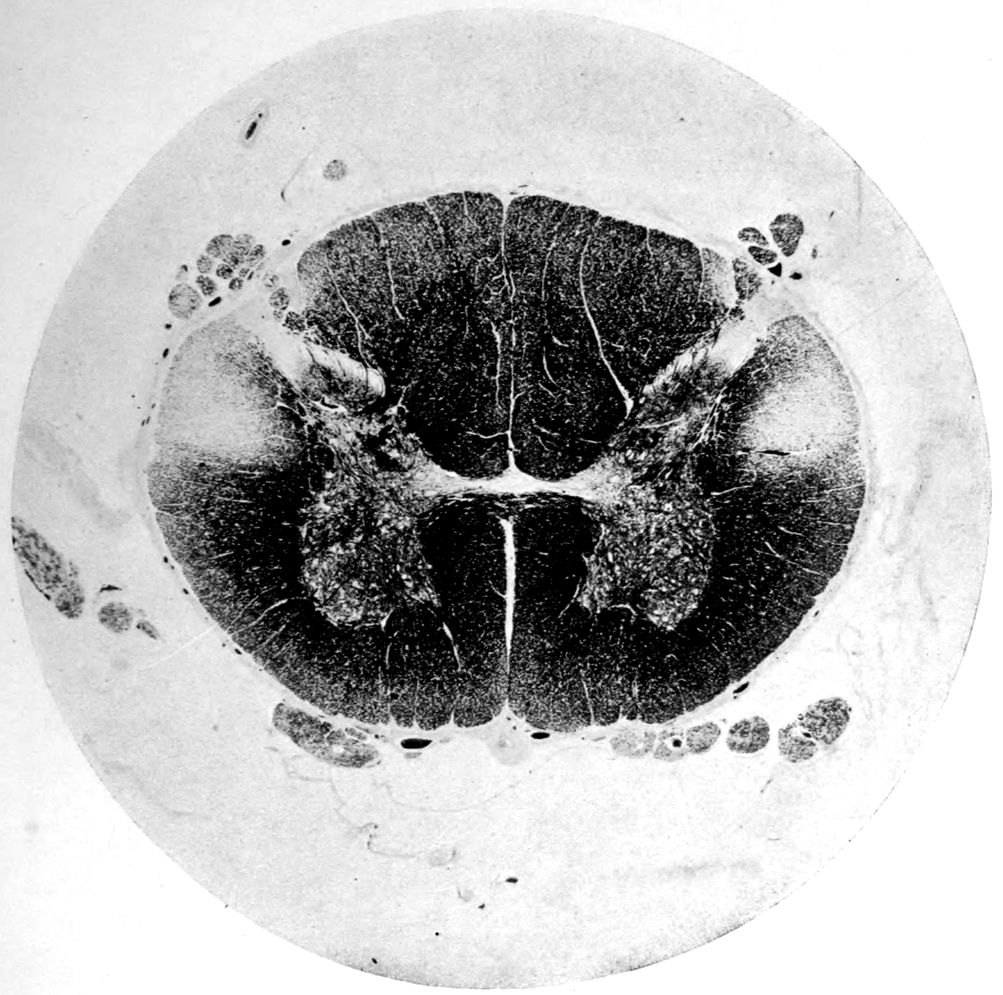

Case 4. James Pierce was an almshouse transfer to the Danvers Hospital in his fiftieth year. He died three years later. The accompanying brain pictures demonstrate so extensive a lesion of the left hemisphere that it is of great interest to determine if possible the genesis and course of his disease. It appears that syphilis had been acquired somewhere about the age of 38 or 40, so that the total duration of the process was between 13 and 15 years. In Pierce’s forty-third or forty-fourth year, he had a shock while walking in the streets of his native city, whereupon he was subsequently transferred to the Danvers Hospital, whose data have been summed up as follows (we are obliged to Dr. Charles T. Ryder for these data):

Summary: Here is a picture made up almost purely of Vascular Neurosyphilis, with Secondary Spinal (Pyramidal Tract) Changes. Doubtless the genesis of this picture is allied to that of Case 1 (Alice Morton) and to that of the terminal vascular complications in a tabetic, Case 2 (Francis Garfield).

The absence of meningeal and parenchymatous (i.e., outside the region of necrosis produced by the vascular disease) lesions is characteristic of an important group of neurosyphilitic diseases. It is clear that the case, although one of extensive lesions, is not one of diffuse lesions in the sense of Case 1 (Alice Morton).

Vascular neurosyphilis—effects of syphilitic thrombosis of Sylvian artery 10 years before death. (Case 4.)

Case 4. (See previous figure for brain lesion.) Three levels of the spinal cord showing unilateral pyramidal tract sclerosis, 10 years after cerebral thrombosis.